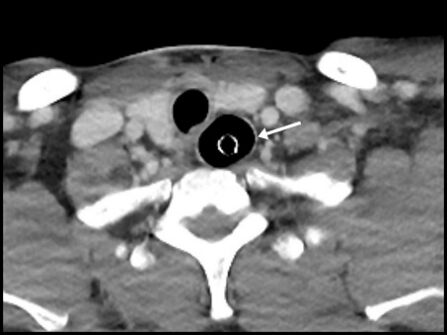

33.某人頭部創傷,到院前心跳停止(out-of-hospital cardiac arrest, OHCA),經心肺復甦術及氣管內管(endotracheal tube)插管治療後,接受電腦斷層檢查,下圖箭號處最適當的敘述為何? (A)食道插管(esophageal intubation) (B)氣管狹窄(tracheal stenosis) (C)食道破裂(esophageal perforation) (D)正常插管後現象(normal postintubation phenomenon)